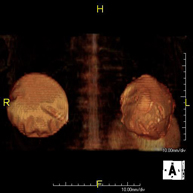

Prueba diagnóstica no invasiva que consiste en la obtención de imágenes de alta definición anatómica de ambos riñones mediante el empleo de un campo electromagnético y ondas de radio (con un emisor y un receptor). No utiliza radiación ionizante. Se realiza para estudiar cualquier lesión localizada en ambos riñones. Normalmente se requiere el uso de contraste paramagnético (Gadolinio) para caracterizar las lesiones. - RM Glándulas Suprarrenales